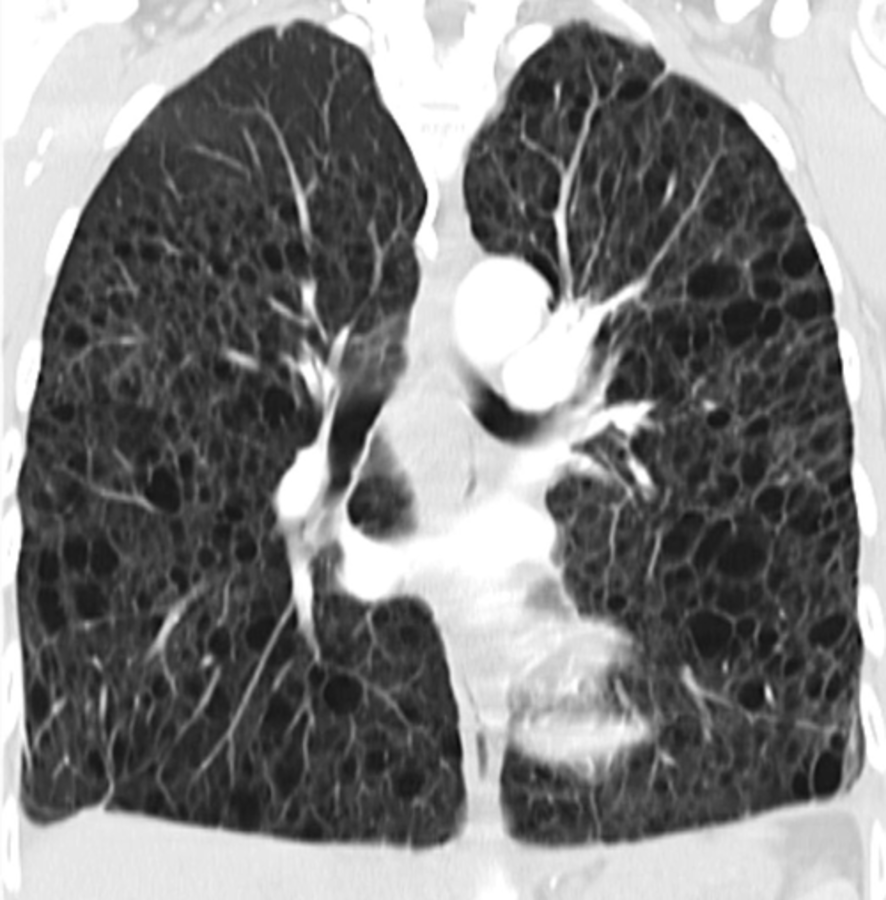

Aber wie gesagt: Erst muss die Dia­gnose sicher stehen. Das hochauflösende CT liefert wichtige Hinweise. Es zeigt multiple dünnwandige Zysten ohne Binnenstruktur, die sich gleichmäßig über beide Lungen verteilen. Aber es reicht allein nicht aus, um die LAM zu sichern. „In manchen Fällen, wenn die Patientin keine Symptome zeigt und das HRCT nur milde zystische Veränderungen, ist es okay, eine wahrscheinliche LAM zu diagnostizieren. Vor allem wenn daraus keine therapeutische Konsequenzen folgen“, sagte der Pneumologe. Voraussetzung ist, dass die Patientin regelmäßig zur Lungenfunktionskontrolle erscheint.

In der Lunge dieser Patientin mit Lymphangioleiomyomatose sind zahlreiche dünnwandige Zysten erkennbar. In der Lunge dieser Patientin mit Lymphangioleiomyomatose sind zahlreiche dünnwandige Zysten erkennbar. © wikimedia/Hellerhoff